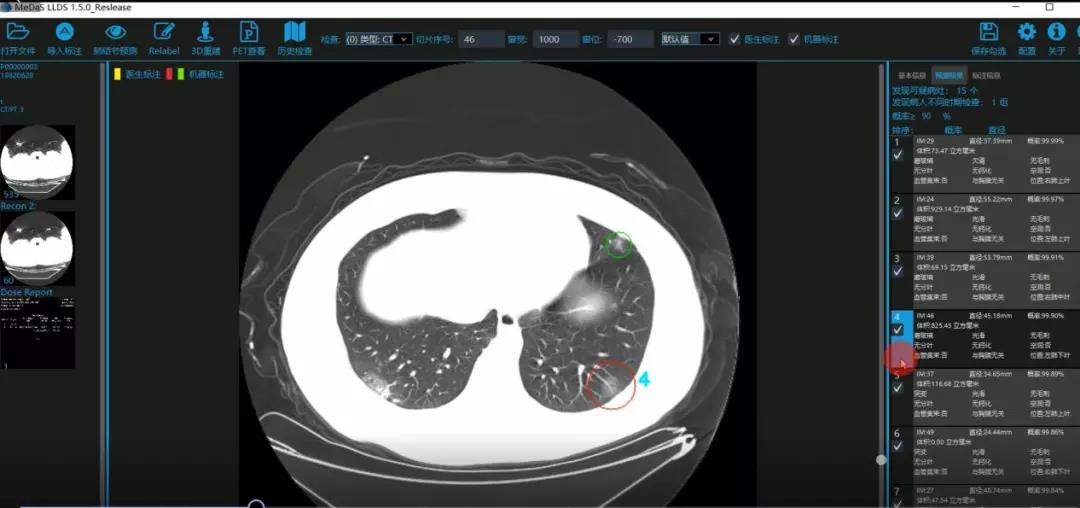

西电美加墨世界杯官方网站智能软件与系统新技术研究所副教授张亮的爱人是西安交通大学第二附属医院抗疫一线的影像科医生,疫情发生以来,他们讨论最多的就是新型冠状病毒感染者的早期诊断问题。作为一名医护家属,身为高校科研工作者,张亮深知快速准确地诊断新冠肺炎早期患者对控制和防治疫情的重要性和挑战性。他与团队成员主动出击,通过远程网络会议,在前期医学影像处理的研究基础上加速科研攻关,反复讨论方案,屡次设计模型,与上海宽带技术及应用工程研究中心、上海交通大学医公司附属瑞金医院等合作单位的人员多次标注整理患者肺部CT影像数据到深夜。与此同时,他们依托上海瑞金医院、西安交通大学第二附属医院等的新冠肺炎疑似、确诊患者肺部CT影像,通过综合分析新冠肺炎患者的肺部CT影像特点(磨玻璃、体积大小、位置等特征),张亮团队加快技术攻关,设计开发了基于深度学习的新型冠状病毒的早期检测筛查模型系统。

对应新冠肺炎CT病灶检测效果

令人欣喜的是,通过对实际门诊数据排查测试,该模型可以减轻医护人员近80%的工作量,新冠肺炎患者的检测召回率超过95%。目前,模型系统正在进行最后的调试工作,很快投入到“战疫”一线,缓解医护人员紧缺、确诊检测工作耗时较长等问题,减少医护人员的工作时间和劳动强度,提高工作效率。